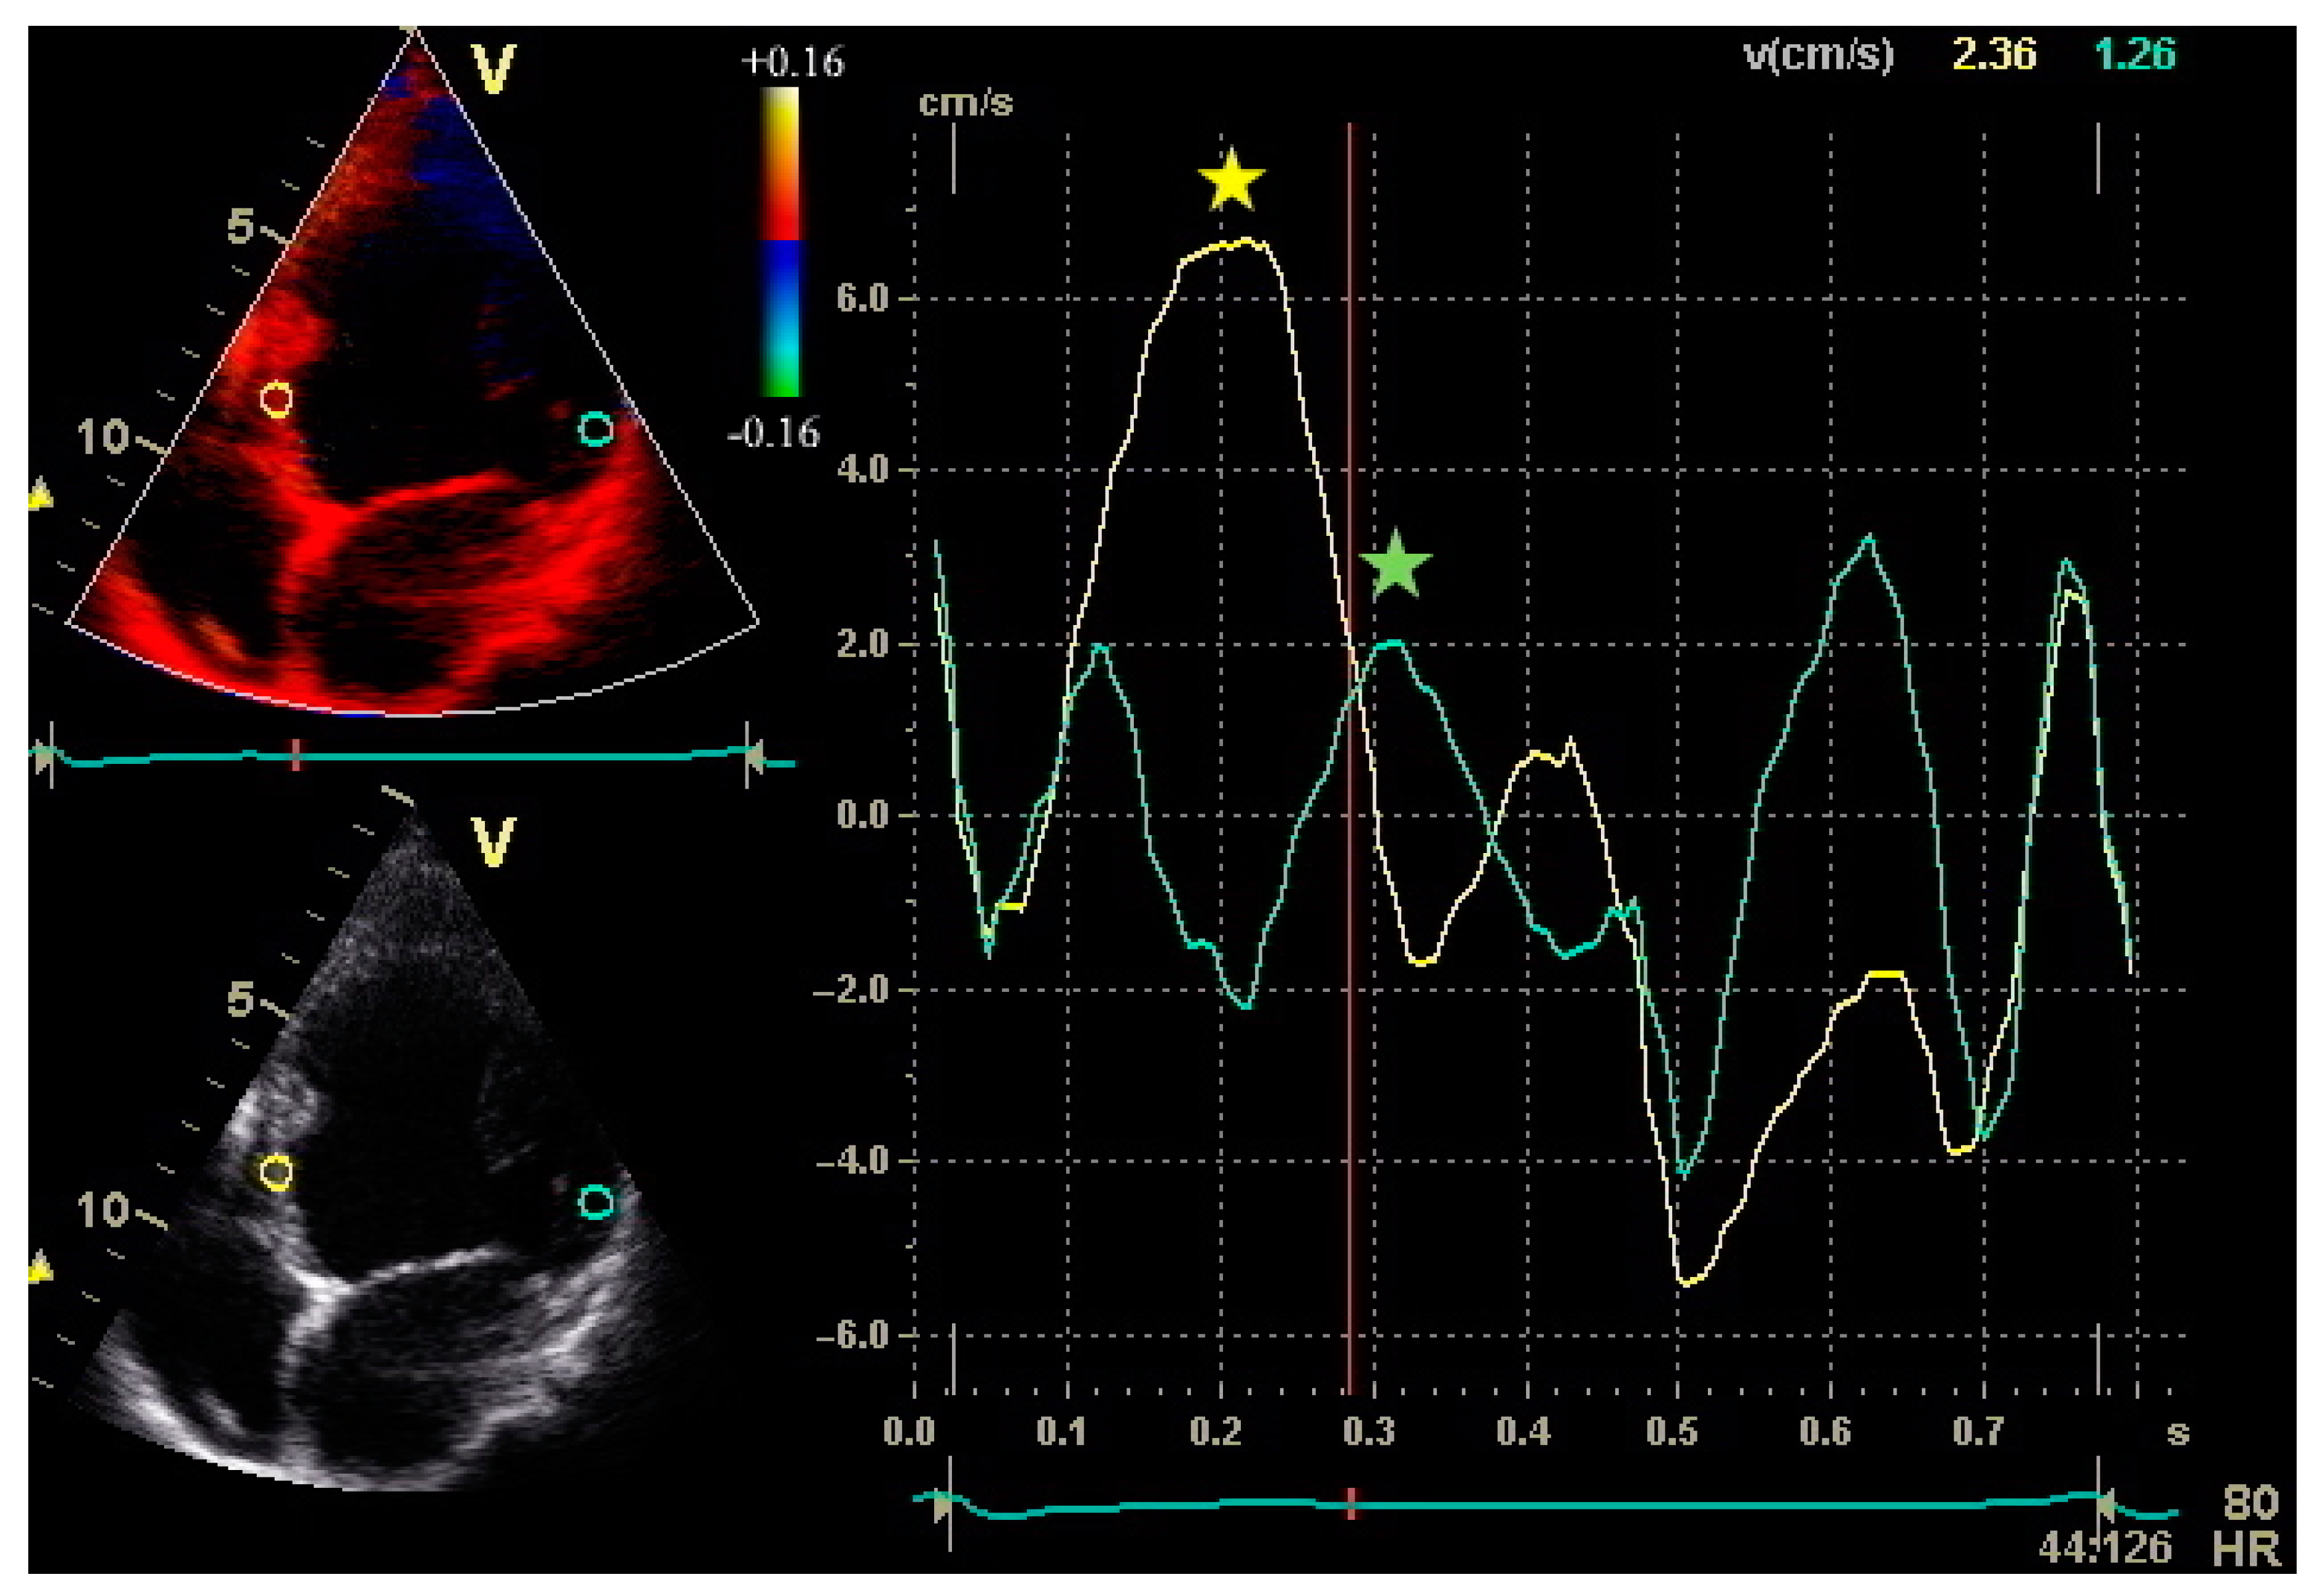

In the past few years, much interest has focused on the implementation of cardiovascular imaging techniques in patient selection for CRT. Table 1 summarizes the main applications, advantages and disadvantages of different cardiovascular imaging modalities which can be used before CRT implantation. Echocardiography has been the most widely used imaging modality to evaluate LV systolic function and mechanical dyssynchrony before CRT implantation. LVEF is calculated by assessing LV volumes from the apical four- and two-chamber views, according to Simpson’s equation. Various echocardiographic methods, including M-mode echocardiography and tissue velocity imaging (Figure 1), and different echocardiographic indexes have been investigated to assess mechanical dyssynchrony [5]. Although the initial studies on LV intraventricular dyssynchrony, assessed by echocardiography, have given promising results in predicting CRT response [5], the PROSPECT trial has raised concerns regarding the widespread use of echo methodologies before implantation, by showing a low feasibility and high inter-laboratory variability of echo dyssynchrony variables [8]. More recently, several two-dimensional (2D) strain imaging and three-dimensional (3D) echocardiographic variables have been proposed to assess LV mechanical dyssynchrony [9,10,11,12]. In particular, global longitudinal strain [9] and the time difference between peak radial strain of the anteroseptal and posterolateral segments [10] have been suggested as predictors of CRT-induced reverse remodelling. Similarly, systolic dyssynchrony indexing using 3D echocardiography seems to be independently associated with long-term prognosis after CRT [11]. In the PREDICT-CRT trial [13], the echocardiographic assessment of apical rocking and septal flash was associated with better survival after CRT. Apical rocking has been described as a short septal motion of the apex early in systole, followed by a long motion to the lateral side, deriving from a late lateral wall activation in patients with left bundle branch block [12,13]. Septal flash has been described as an early posterior movement of the interventricular septum towards the LV, caused by an early contraction of the right ventricular (RV) free wall in patients with left bundle branch block [12,13]. In the PREDICT-CRT trial, both apical rocking and septal flash were visually assessed, and their identification was associated with favourable long-term prognosis in patients undergoing CRT [13]. More recently, systolic septal myocardial stretching by speckle tracking echocardiography was shown to be a predictor of CRT response with an additive predictive value over apical rocking [14]. Despite these encouraging results, the prognostic role of echocardiographic dyssynchrony indexes is still debated. In a recent study, radial strain-guided LV lead positioning, combined with multimodality imaging, did not provide a significant improvement in CRT response and clinical outcome measures [15]. Moreover, although several echo dyssynchrony indexes have been studied, up to now none have been validated for CRT patient selection beyond current guidelines [1]. Therefore, at present it is not recommended that CRT should be withheld from patients who meet the standard selection criteria because of negative results of an echocardiographic dyssynchrony evaluation [16].

Figure 1.

Peak systolic velocities of the septum and lateral wall by Tissue Velocity Imaging from the apical four-chamber view in a patient with non-ischaemic dilated cardiomyopathy. Sample volumes are placed in the basal portions of the septum and lateral wall. The septal-to-lateral delay is an index of intraventricular dyssynchrony and can be calculated as the difference between time to peak velocity of the septum and lateral wall.